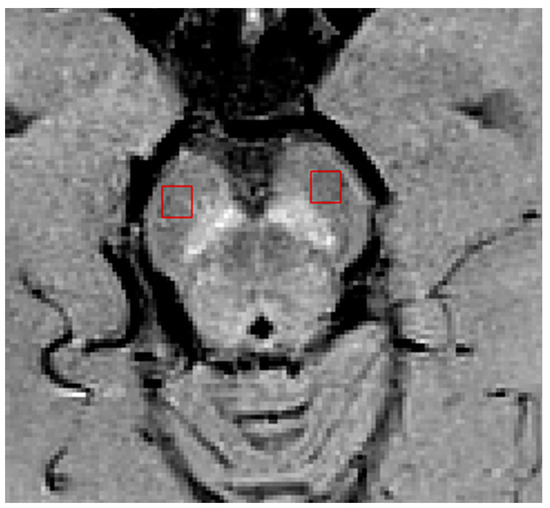

| QSM | T2* | Phaave | ||||||

|---|---|---|---|---|---|---|---|---|

| SN1 | S0 | SN1 | S0 | SN1 | S0 | |||

| 64CH | Older | Mean (std) | 90.20 (33.01) | 136.99 (43.38) | 36.02 (5.86) | 25.26 (5.04) | −0.02 (0.01) | 0.02 (0.02) |

| Young | Mean (std) | 53.16 (29.19) | 85.52 (37.27) | 38.86 (4.49) | 28.94 (4.85) | −0.02 (0.01) | 0.03 (0.02) | |

| p-value a | <0.001 * | <0.001 * | 0.55 | 0.13 | 0.29 | 0.57 | ||